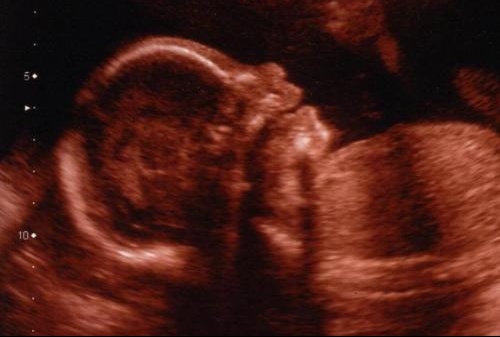

Echographie bebe bouche ouverte-Je viens poster ici en espèrant que vous saurez me rassurer Il s'agit de ma petite soeur qui est enceinte pour novembre, à l'échographie du second trimestre, on a vu que la bouche de sa petite était toujours ouverte, on n'a pas mesuré la clarté nuquale (au premier trimestre, elle faisait 12) L' endoscopie digestive haute est l'observation de l'intérieur de l'œsophage, de l'estomac et du duodénum (première partie de l'intestin grêle) Cet examen est également nommé "endoscopie œsogastroduodénale" ou "fibroscopie œsogastroduodénale", "gastroscopie"On réalise cet examen grâce à un endoscope ou gastroscope introduit par la bouche ou le nez

Vincent était ravi, on s'est tenu la main fort fort, j'ai encore pleuré un peu au début Puis j'ai profité du scénario, des plans séquences On l'a vu ouvrir et fermer la bouche On a bien vu ses yeux, ses mains, doigts de pieds L'infirmière était super !!Quand le bébé tire la langue, il ouvre sa bouche et de la salive peut glisser sur son menton "C'est ce qu'on appelle le bavage" indique Gaëlle Malécot Cette émission involontaire de salive par la bouche est normale chez le bébé et disparaît normalement avant l'âge de 3 ou 4 ans Echographie connaître le sexe de votre bébé J'en ai une où on voit bien le nez et bouche ouverte avec petit bout de langue 🤣 Ton écho à l'air semblable !

Lors de ma dernière échographie (29 SA) ma gynécologue a pu constater que mon bébé, encore une fois, avait la bouche ouverte et interposait souvent sa langue entre ses deux lèvres Lors de l'échographie précédente, il avait déjà la bouche ouverteLe seconde échographie de grossesse, dite échographie morphologique, est une étape importante du suivi de grossesse car elle permet de déceler d'éventuelles malformations fœtales Les mouvements enregistrés par échographie et comme signe d'un bébé qui pleure sont sa bouche ouverte, sa langue baissée, son menton vibrant et sa respiration devenant irrégulière Les différentes expressions sur le visage de Si Kecil, y compris les pleurs, peuvent être vues lorsque Bunda effectue un examen échographique de la grossesse